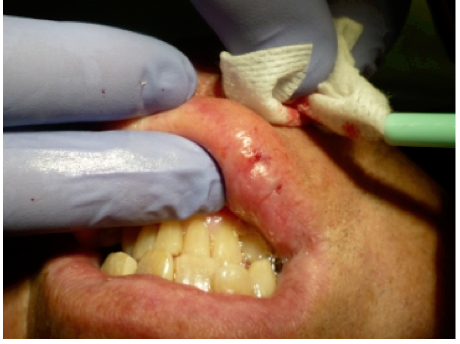

Topical anesthetic was applied to the lesion (Figure 5). Local anesthesia with 2% lidocaine with a 1:100,000 epinephrine mixture was administered by infiltration (Figure 6). Note bleeding at the injection sites in Figure 6 and Figure 7. This reminded the surgeon to be especially careful and mindful of the patient’s condition, which required anticoagulants.

To achieve the optimal laser-tissue interaction, the laser handpiece was held strictly at a 90° angle to the lesion (Figure 7 and Figure 8).

Figure 6 Local anesthesia was given by infiltration. Note the bleeding in the injection sites; the surgeon had to be mindful of the patient’s history of taking blood thinners for his atrial fibrillation.

Figure 6

Figure 7 The CO<sub>2</sub> laser handpiece was held perpendicular to the lesion at a 1.5-mm to 3-mm tip-to-tissue distance.

Figure 7